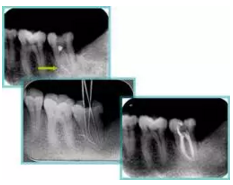

2. X 線片

共有 4 張 X 線片,分別是術(shù)前、診斷絲 、主牙膠尖確認(rèn)、術(shù)后。

( 1 )術(shù)前:術(shù)前 X 線片用來了解牙齒的大概情況。術(shù)前預(yù)期為多根牙時 X 線片應(yīng)偏頭拍攝。

( 2 )診斷絲:根據(jù)術(shù)前 X 線片進(jìn)行開髓、根管的初步預(yù)備后,需要插入診斷絲,用來指示工作器械位置。常用 10 號或 15 號擴(kuò)大器作為診斷絲插入牙髓腔。

( 3 )主牙膠尖確認(rèn):通過術(shù)前預(yù)期和診斷絲診斷,明確工作長度、牙根走向,進(jìn)行根管預(yù)備。之后應(yīng)進(jìn)行主牙膠尖(中銼)確認(rèn),已明確根管是否適合充填。

( 4 )術(shù)后:觀察治療效果。